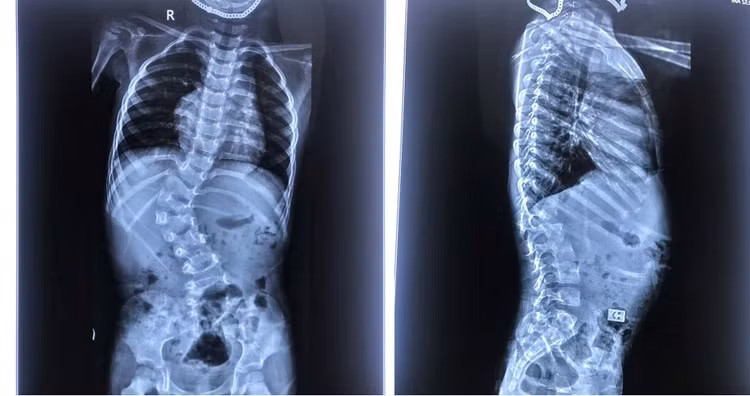

![]() |

| Hình X quang cong vẹo cột sống - Ảnh BVCC |